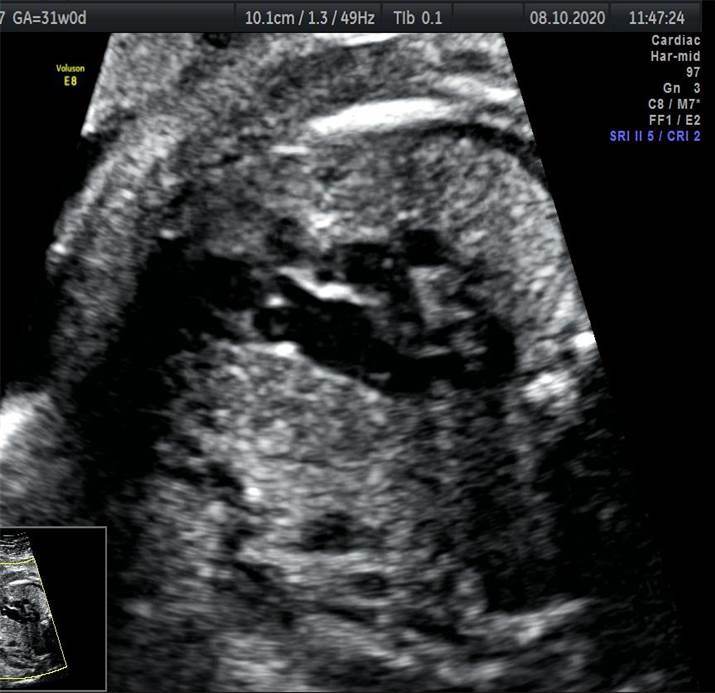

Вопрос 2

Проанализируйте изображения и видеоклипы грудной клетки плода в 31 неделю, установите диагноз и дальнейшую тактику ведения беременности